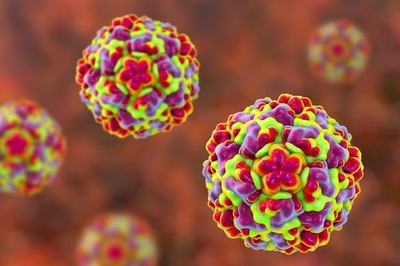

rhinovirus의 원인은 대부분 바이러스이고 rhinovirus가 가장 일반적입니다.주로 환자의 재채기, 기침으로 인한 공기 전염성이지만 때로는 손이나 입을 맞추기를 통해 직접 감염되기도 합니다.추운 기후, 찬바람, 낮은 습도, 과로, 수면 부족, 영양 부족 등으로 발병하기 쉽습니다.